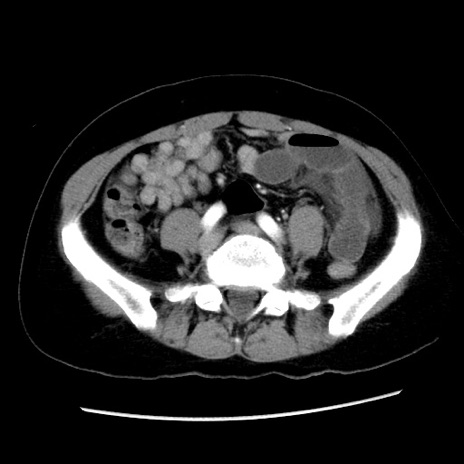

症例10(横断像)

【症例】 50歳代女性

【主訴】 腹痛

【現病歴】前日生レバーを食べた。今朝に排便あり。 昼前に突然発症の腹痛を生じ、当院救急外来を受診した。

【既往歴】 子宮筋腫にてで子宮全摘後

【身体所見】 意識清明、腹部:平坦、軟、下腹部やや左を中心に圧痛・反跳痛あり、筋性防御あり

【データ】WBC 7800、CRP 0.07